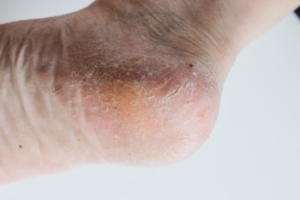

Treatment For Cracked Heels

Cracked heels develop when the skin on the back of the foot becomes dry, thick, and less flexible, eventually splitting under pressure. These splits can be tender, unsightly, and sometimes deep enough to cause bleeding or infection. Restoring comfort begins with softening the skin so it can heal. Warm water soaks help loosen the outer layers, and applying a rich, emollient cream afterward locks in moisture. Regular use of products that gently break down thickened skin can also improve texture over time. Wearing supportive footwear with closed backs helps reduce pulling on the skin and prevents further cracking. Keeping socks on after moisturizing encourages better absorption and protects healing tissue. Because deeper fissures can lead to complications, especially for individuals with diabetes or circulation concerns, any persistent or painful cracking deserves attention. If your cracked heels are not improving or feel increasingly uncomfortable, it is suggested that you see a podiatrist for proper treatment and guidance.

Cracked Heels

It is important to moisturize your cracked heels in order to prevent pain, bleeding, and infection. The reason cracked heels form is because the skin on the foot is too dry to support the immense pressure placed on them. When the foot expands, the dry skin on the foot begins to split.

Cracked heels may make you want to think twice about showing off your feet in warmer weather. However, cracked heels may be harmful to more than just the appearance of your feet. If deep fissures and cracks develop in your heels, they may make walking and standing painful for you. Additionally, these openings make way for germs to enter through your skin and cause infection.

There are several different causes of cracked heels. One of the most common reasons for this ailment is dry skin. This problem may make your keeps feel rough tight and itchy. Dry skin may be caused by cold air, extremely hot water, harsh soaps, and aging. Skin disorders such as eczema and psoriasis may eventually lead to dry skin. In some cases, complications may arise from cracked heels. Some of these complications are a loss of feeling in the heel, cellulitis, or a diabetic foot ulcer.

There are ways you can try to prevent getting cracked heels. One of the best ways to do so is to avoid wearing flip flops and sandals because these shoes increase your risk of drying out your feet. You should also avoid wearing shoes with a tall skinny heel, because these shoes cause your heel to expand sideways. At night, you should slather on a thick moisturizing cream on your feet and then cover them in socks to keep your feet moisturized overnight. Drinking water to stay hydrated is also a good way to ensure that your skin doesn’t become dry.

If you suffer from a severe case of cracked feet, you should make an appointment with your podiatrist to see what treatment methods are best for you.